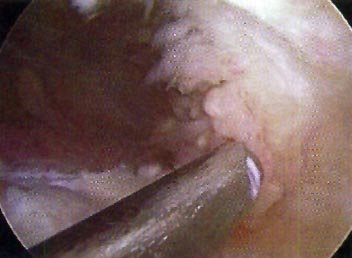

Se envió material para aislamiento, tipificación, cultivo y antibiograma. (Fig. 1-2- y 3)

Figura 1: Exploración artroscópica.

Figura 2: Debridamiento. Toma de Figura muestra. .

Figura 3: Importante reacción sinovial